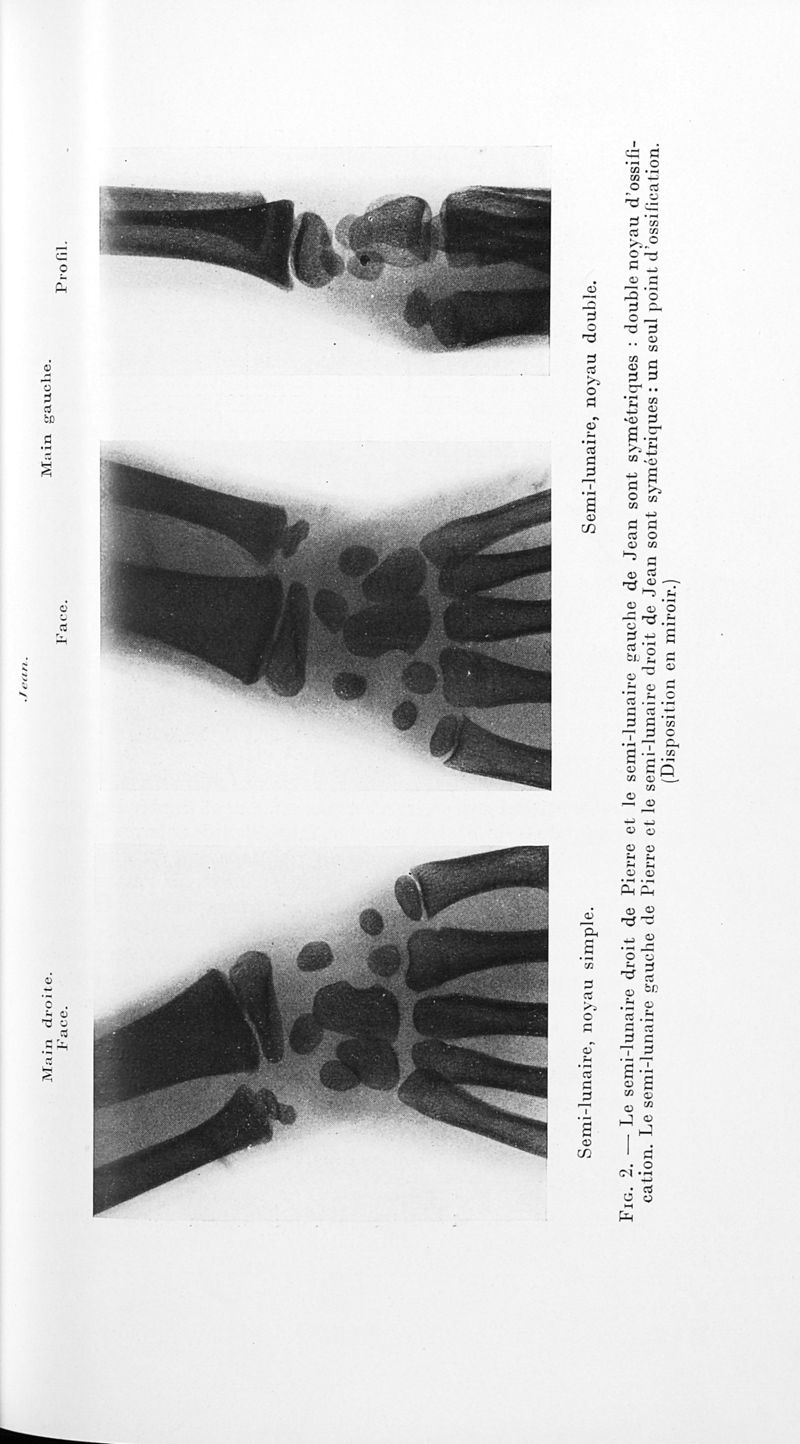

Bulletins de la société de pédiatrie de Paris

Tome trente-sixième. - Paris : Masson et Cie, 1938.